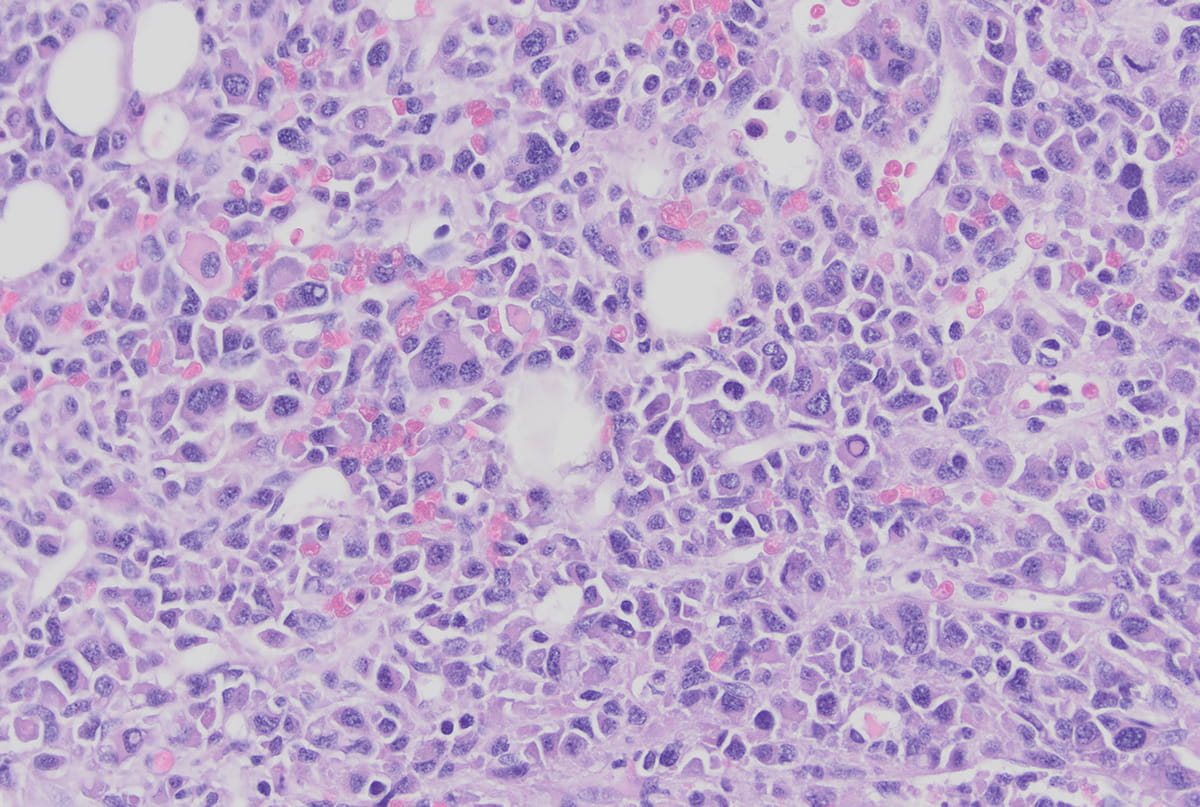

• microscopy image of myeloma in plasma cells

Tracing the Story of Myeloma

The Indiana Myeloma Registry charts new variables of the disease in pursuit of more effective therapies.

Matthew Harris  |  Dec 21, 2023